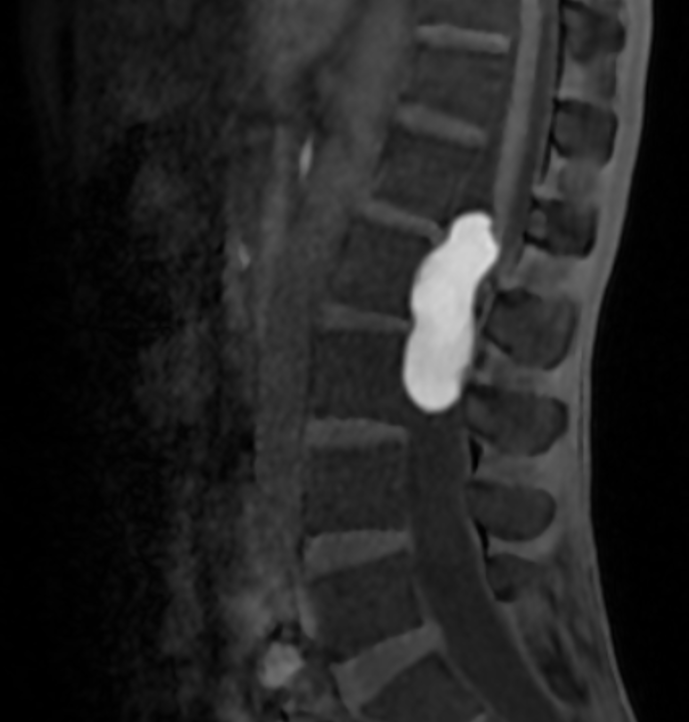

SAGITTAL T2

SAGITTAL T1

T1 PRE CON

T1 POST CON

MRI is the modality of choice for evaluation of spinal epidermoid cysts. Although classically described as T1 hypointense, T2 hyperintense lesions with diffusion restriction, imaging appearances may be variable, particularly in chronic or protein-rich lesions.

In the present case, the lesion demonstrates T1 hyperintensity and T2 hypointensity, an atypical appearance attributed to dense keratinaceous debris, cholesterol crystals, high protein concentration, and chronic desiccation, resulting in shortening of T1 and T2 relaxation times. Such lesions are described as atypical or “white” epidermoid cysts.

Dixon fat-phase imaging demonstrates absence of fat signal, effectively excluding a dermoid cyst and supporting the diagnosis of an epidermoid cyst.

Post-contrast imaging shows no significant internal enhancement, supporting a non-neoplastic cystic etiology.